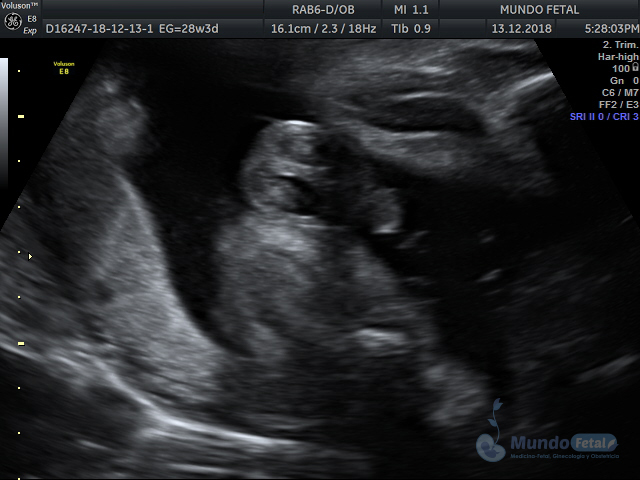

Mediante esta técnica ultrasonográfica, evaluamos en tiempo real al bebe y monitoreamos electrónicamente la frecuencia cardiaca fetal, vigilando los siguientes parámetros: